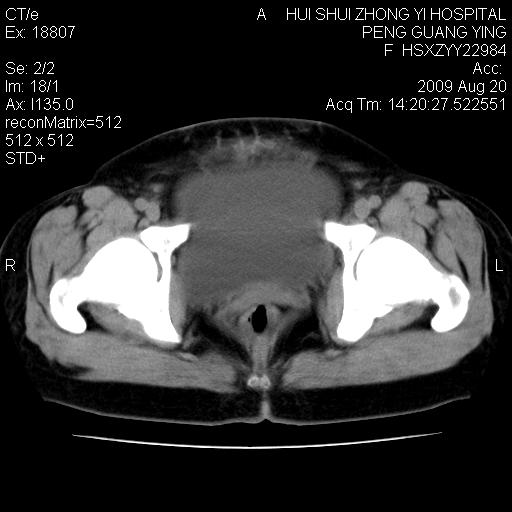

标题: CT21707:女,42岁,因发现下腹部包块2月。 [打印本页]

标题: CT21707:女,42岁,因发现下腹部包块2月。

来源卵巢--畸胎类肿瘤

病史不全面,病灶来源可能是子宫或卵巢,若临床有剖腹产、痛经史,则更支持前者,亦更支持子宫腺肌症

目前的影像表现显示肿块位于腹腔及盆腔,但具体定位,分清来源较困难,是否来源于卵巢、子宫无法定论,子宫直肠及子宫膀胱周围脂肪间隙尚较清晰,如果患者有过腹腔好或者盆腔手术史,也可以形成不典型的血中,最好手术后定为定性,我期待结果。